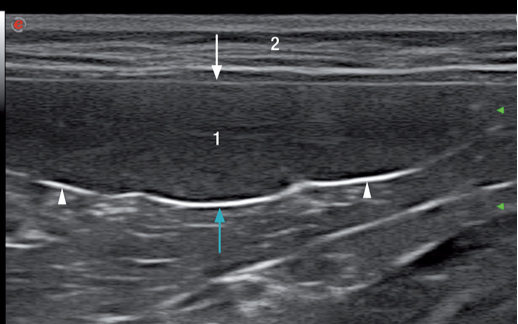

脾脏含有被膜、小梁和实质组织(红髓和白髓组成)。脾脏的血管包括动脉和脾静脉,脾动脉起源于腹主动脉,脾静脉汇入到门静脉。脾动脉和脾静脉在脾门处进入脾脏,脾门位于脾脏的脏器面中间(图3.视频2)。脾门淋巴结引流脾脏的淋巴液,然后通过淋巴管注入腹腔干,最后汇入乳糜池。

健康动物的脾脏边界清晰,被膜薄而光滑(图2和图3)。脾脏的脏器面的轮廓不规则,是因为在脾门的地方有血管进出。横断面上的脾脏呈三角形(图4)。二维超声图像上很难看到脾动脉进入脾脏,需要使用彩色多普勒才能识别脾动脉(图3)。